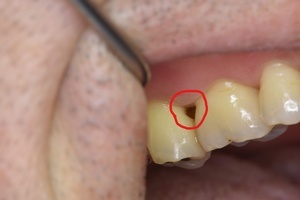

歯の根の治療に約1年通院しており、神経(歯髄)を取ったはずなのに、いつまでも

痛みが取れず、心配になり当院に来院。お話を伺うと、ホームページでマイクロスコープを

使用する歯内療法専門医院だったそうです。

初診時(デンタル) 初診時(CT)